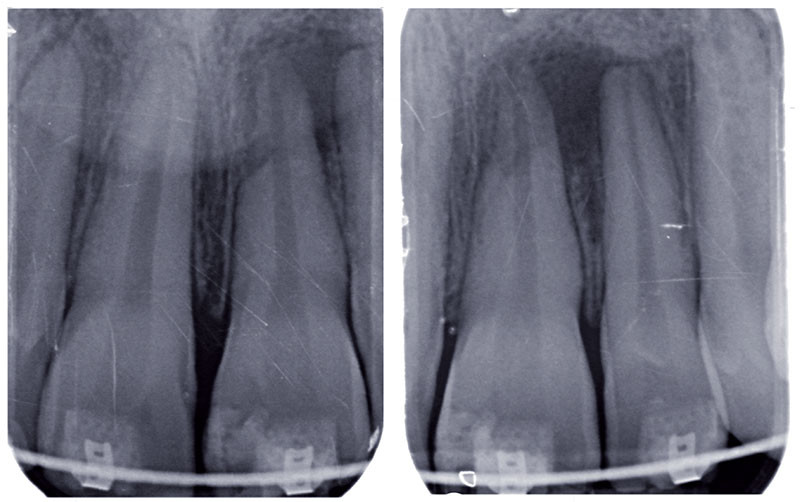

Le Dr Stéphane Simon dans cette nouvelle réponse d'expert revient sur la lésion apicale ou parondie apicale traitée tous les jours par les praticiens. Cette grosseur bénigne qui survient au niveau de la racine dentaire est provoquée par le système immunitaire On l'appelle kyste apical, granulome, lésion d'origine endodontique ou encore lésion apicale

Management of Apical Periodontitis Healing of Posttreatment Periapical Lesions Present 1 Year. Le granulome dentaire est une lésion inflammatoire à la racine d'une dent, causée par une infection bactérienne Aujourd'hui, plongeons-nous dans l'univers complexe d'une affliction dentaire relativement commune mais souvent mal comprise: la lésion apicale

Figure 1 from Endodontic Periapical Lesion An Overview on the Etiology, Diagnosis and Current. Le Dr Stéphane Simon dans cette nouvelle réponse d'expert revient sur la lésion apicale ou parondie apicale traitée tous les jours par les praticiens. Le traitement peut inclure une intervention endodontique ou une extraction.